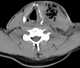

Neck infection